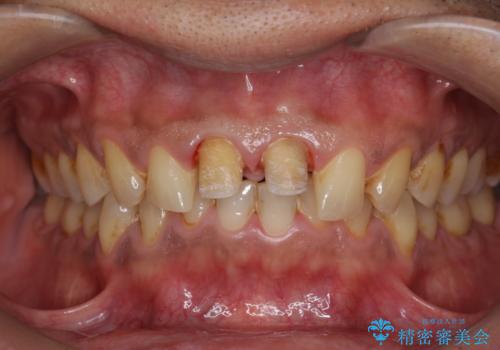

- 体調により前歯部の歯ぐきから出血や膿が出ることの改善を求めて来院されました。

X線写真より、根尖部に透過像が認められ根管治療・ファイバーコア築盛・セラミッククラウンの作製が必要な状態です。

歯ぐきからの出血・排膿がある場合、根管内の感染や 歯肉炎・歯の破折などが考えられます。

X線検査や歯周組織検査などを行い適切な治療を行うことで良好な結果を得ることができます。